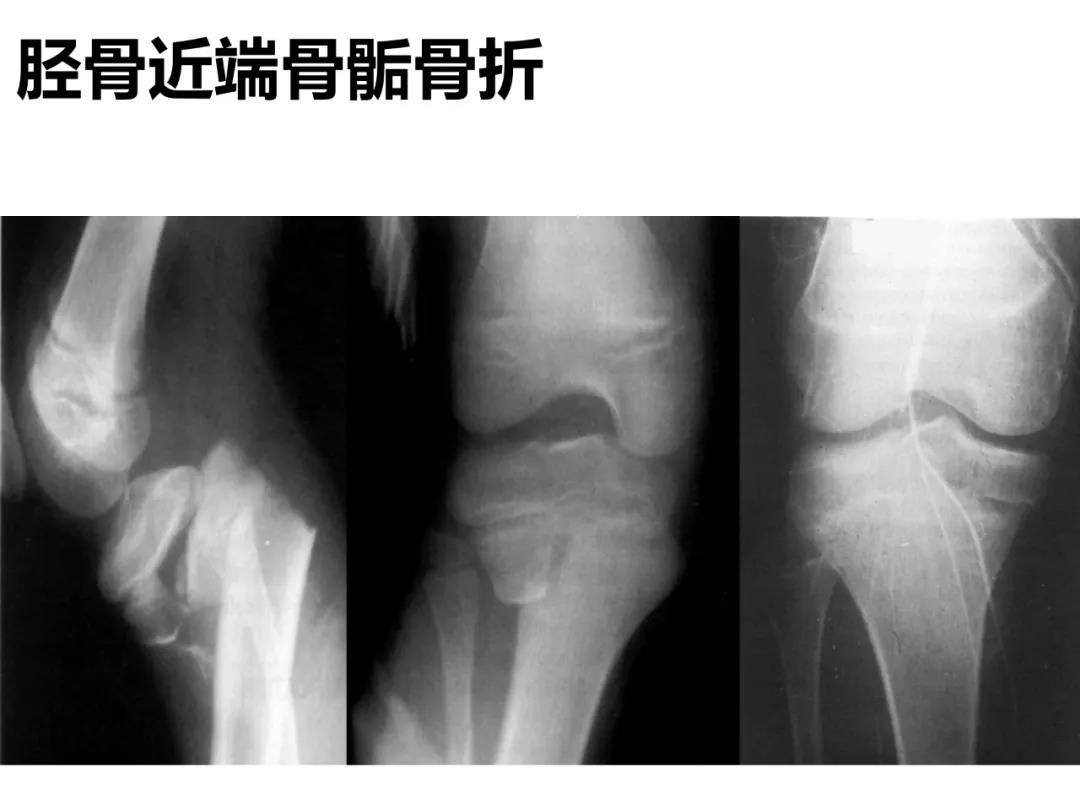

小儿骨科X线片汇总,临床读片宝典!